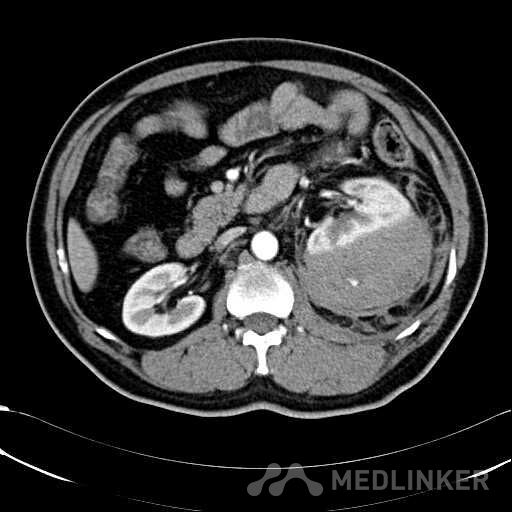

患者是54岁男性 主 诉: 突发左腰部疼痛3小时。 现病史: 缘于入院前3小时患者无明显诱因出现左腰部剧烈疼痛,无向他处放射,与活动及体位无明显关系,伴有腹胀、恶心、呕吐,无头痛、头晕,无人事不省、口吐白沫,无胸闷、胸痛、咯血,无发热、畏冷、寒战,大小便未解,肛门无停止排气,遂就诊我院,查“泌尿系彩超:左肾实质及不均质回声区,范围约9.4*4.1cm,界不清,内未见明显血流信号”,为进一步治疗,门诊拟“左肾占位”收住入院,发病以来,患者精神欠佳,未进食,大小便如前述,体重无明显改变。 患有“高血压病”7年,规则服药治疗(具体不详),监测血压情况不详。 T: 36.5 ℃ P: 65 次/分 R: 20 次/分 BP: 154/94 mmHg 双肾区皮肤无红肿、破溃及隆起,双肾肋下均不能被触及,左侧肾区叩击痛明显,右侧肾区无叩击痛,双侧肾区未闻及血管杂音。膀胱区无隆起,无压痛,耻骨上膀胱区叩诊空虚。外生殖器发育正常。 2016-04-12 泌尿系彩超:左肾实质及不均质回声区,范围约9.4*4.1cm,界不清,内未见明显血流信号。 04-12血常规:血红蛋白 151 g/L,白细胞 16.80 10^9/L,中性粒细胞百分比 84.90 %。急诊生化:白蛋白 39.8 g/L,葡萄糖 9.46 mmol/L。